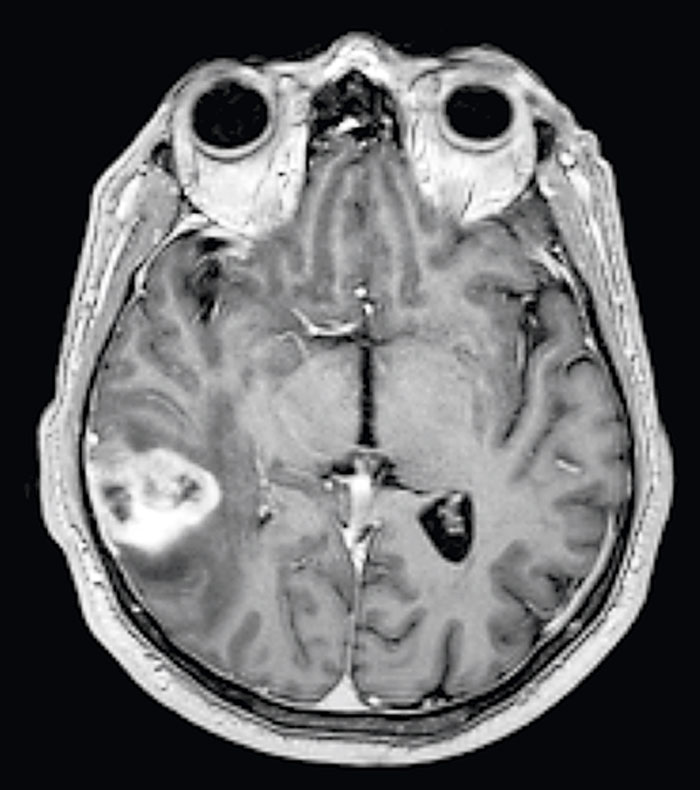

Fallrapport 2 [58] (Fakta 1) rör en 21-årig man som sökte med svår huggande smärta sedan 2–3 veckor. Huvudvärken kom i attacker och satt bakom höger orbita. Klinisk undersökning/laboratorieprov var u a. Patienten uppfyllde kriterierna för klusterhuvudvärk, och terapi med sumatriptan i tablett- och injektionsform sattes in. Han svarade på injektionsbehandlingen med minskning av huvudvärken efter 15–20 minuter, men attackfrekvensen var oförändrad. Ingen förebyggande behandling gavs. Eftersom attacker­na fortsatte sökte han igen. DT-undersökning gjordes efter tre veckor och visade högersidig maxillarsinuit (Figur 2). Punktion utfördes och visade pus och växt av S pneumoniae. Huvudvärks­attackerna försvann helt efter punktionen och antibiotikaterapin. Han är huvudvärksfri vid uppföljningarna efter flera år trots utsättning av läkemedel.

Figur 2. DT skalle visar en högersidig akut maxillarsinuit.